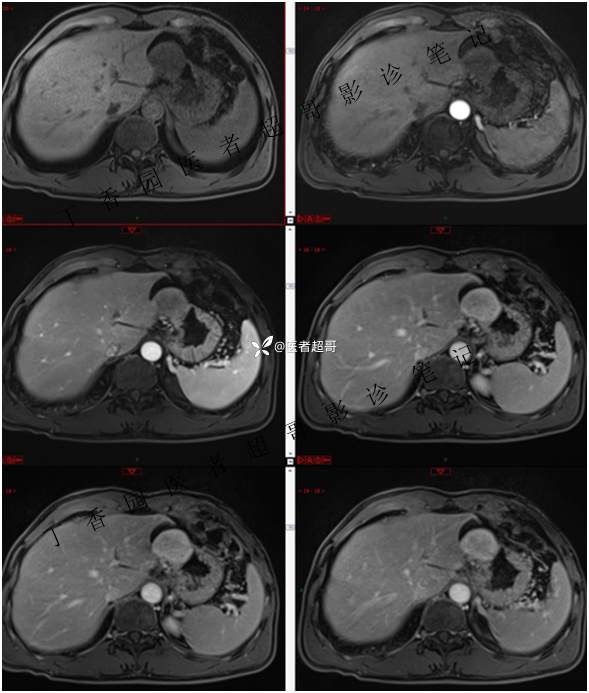

肝胃间隙肿瘤,间质瘤?平滑肌瘤?还是鞘瘤?有结果,请分析!

主 诉:查体发现肝占位3天。

现病史:患者于3天前查体行肝胆脾胰肾彩超示肝内实性占位,无恶心、呕吐,无发热、寒战,无腹胀、腹泻,进一步于医院行上腹部CT增强示:肝胃交界处肿块。未行特殊治疗。今患者为求进一步治疗,来我院就诊,门诊以“肝占位性病变”收入院。患者自发病以来,神志清,精神可,饮食睡眠可,二便可,体重近期未见明显变化。